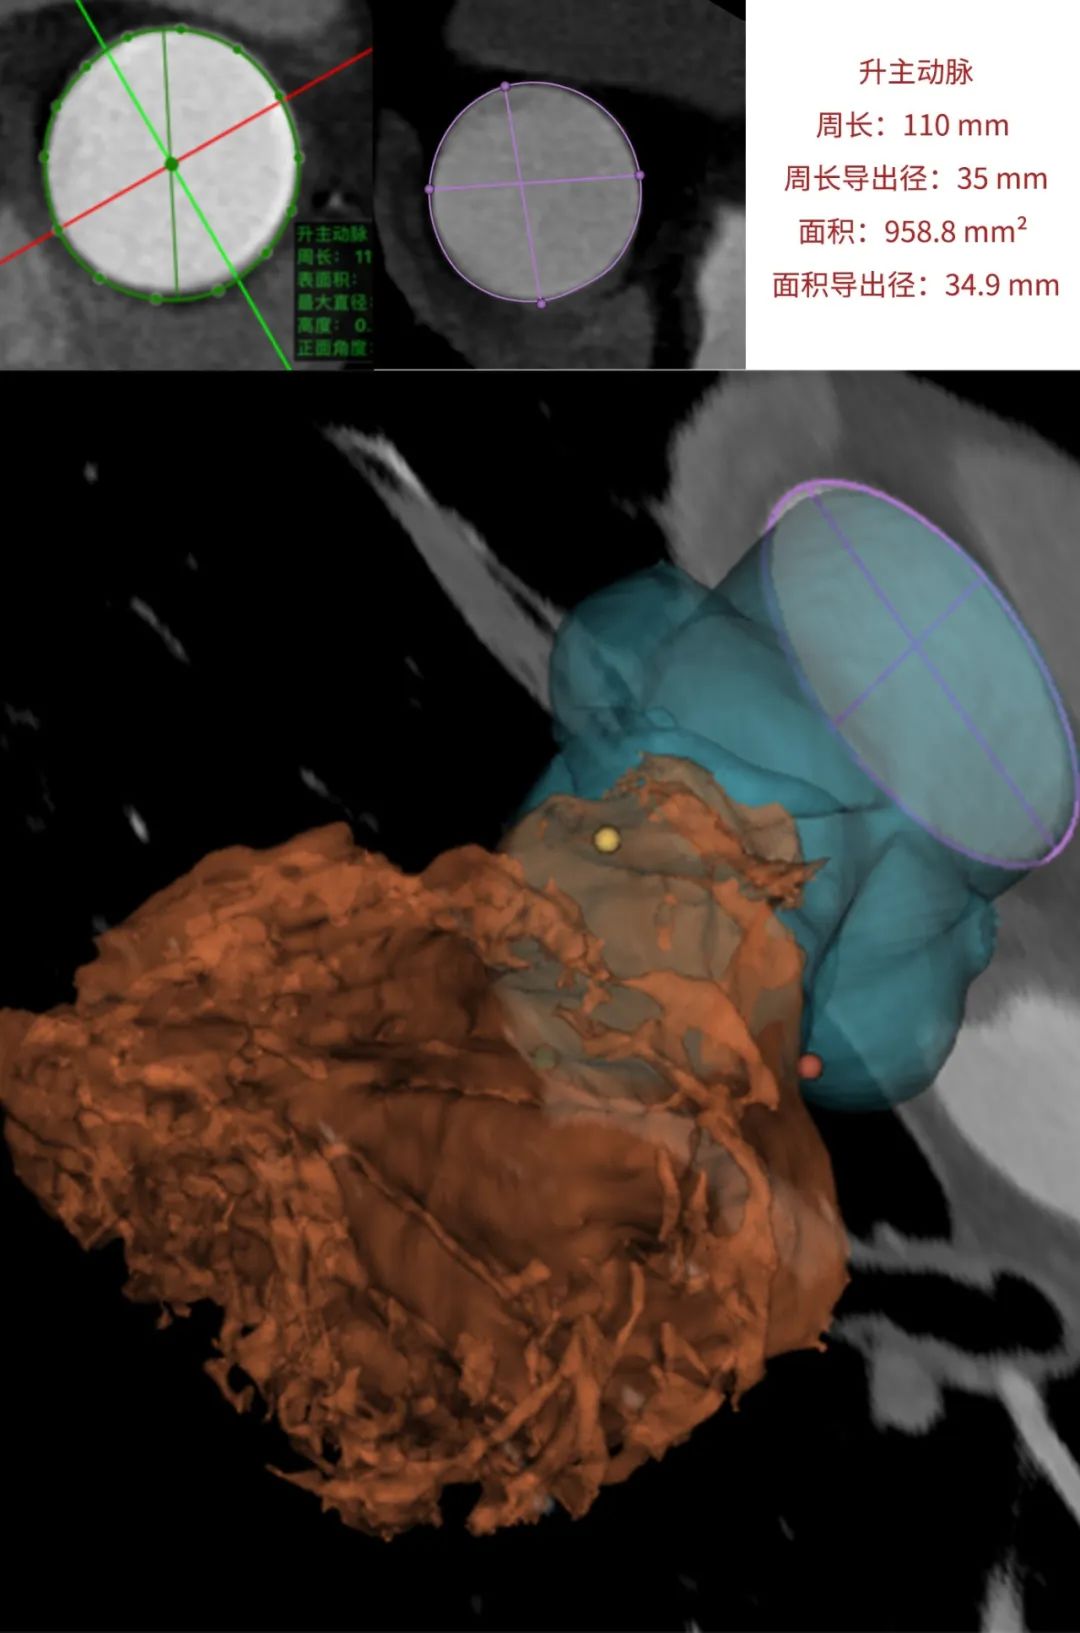

临床团队同时使用了基于医生手工描点的围术期影像评估软件和基于人工智能的瓣膜疾病围术期分析辅助决策软件进行术前影像学评估。

通过术前测量,对病例深入分析,结合人工智能术前分析辅助决策软件进行三维和二维图像融合,郭应强教授指出本例手术存在以下难点: